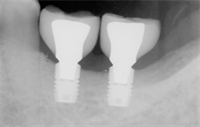

In our daily implant practices we are often confronted with patients who meet the ideal criteria for implant treatment, but have a limited height of bone.  Bone grafting may partially solve this issue, but bone grafting can be expensive, time-consuming, is always uncomfortable for the patient and can involve inherent risks.

The use of short dental implants can often avoid the problems associated with bone grafts - but can it really be that simple?  This course will show you the how's and why's of short implants.